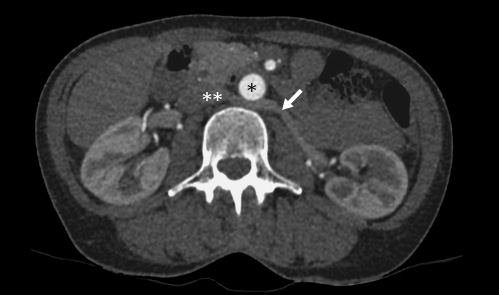

From 221 patients who underwent laparoscopic donor nephrectomy between 2011 and 2017, 11 (4.98%) showed the feature of a retroaortic left renal vein (Fig. 1). In 8 patients (72.7%) decision for left kidney donor nephrectomy was made.